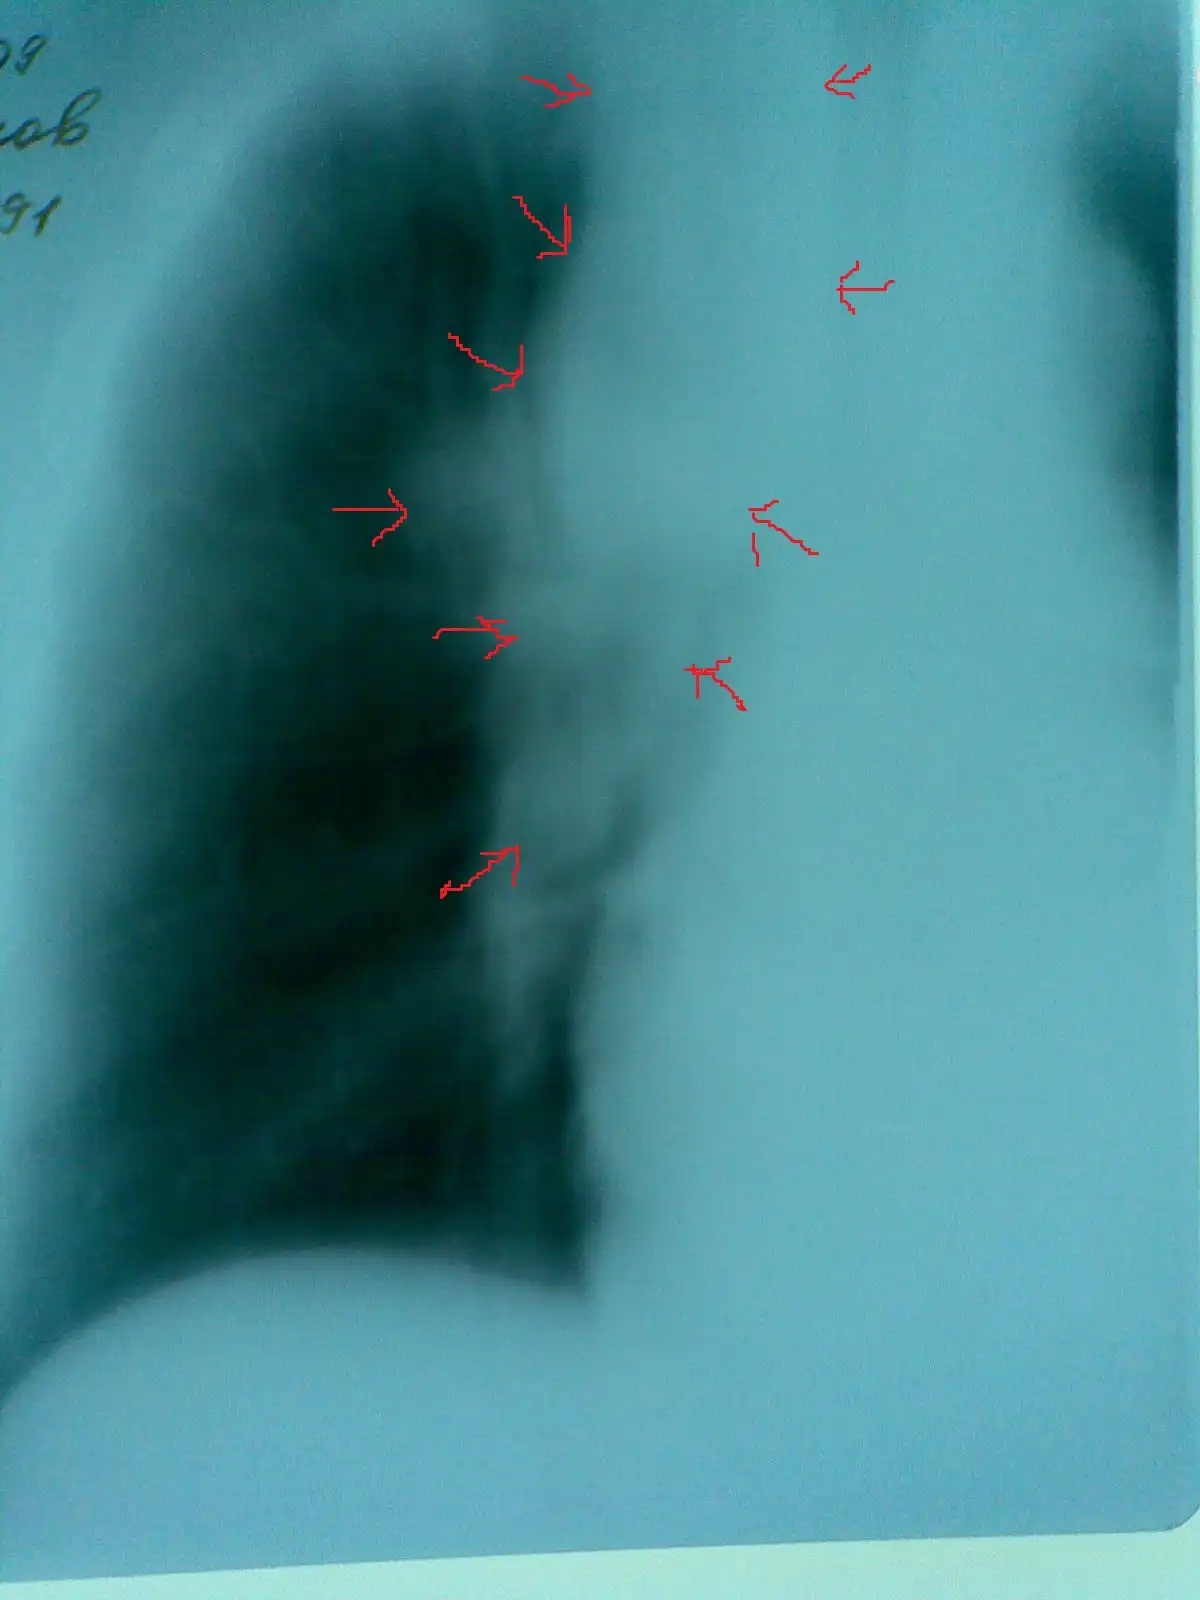

Метастатическое поражение легких из рака почек: